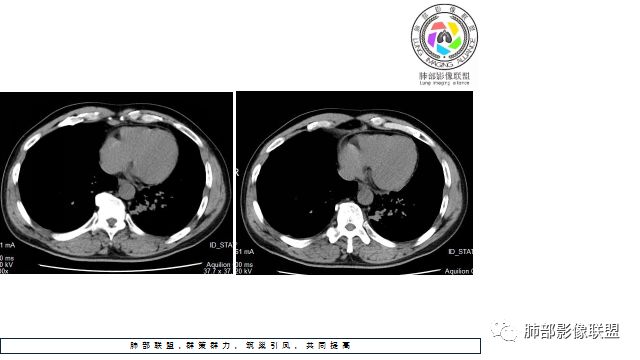

1.左下肺门区巨大肿块,支气管显示不清,轻度阻塞性炎症,没有明显肺不张,提示管腔受压狭窄可能性大于堵塞,这较少见于鳞癌。

2.病灶边缘光滑,未见明显分叶、毛刺,未见明显强化,这符合腺癌影像学特点,却符合神经内分泌癌表现。

3.病灶内密度均匀,轻到中度均匀强化,大病灶未见明显液化坏死区及空洞,不符合鳞癌而符合小细胞肺癌特点。

4.病灶内有肺动脉走形,血管局部受压,未见破坏,病灶乏血供,呈血管包埋或血管造影征;侵袭性力强及破坏力弱、血管漂浮都符合SCLC,所以鳞癌的可能性也不大。

5.左肺门块影或淋巴结肿大,竭力挤兑肺门血管结构,呈冰冻肺门;有时候SCLC可以单独呈现冰冻肺门,而没有没有冰冻纵隔。